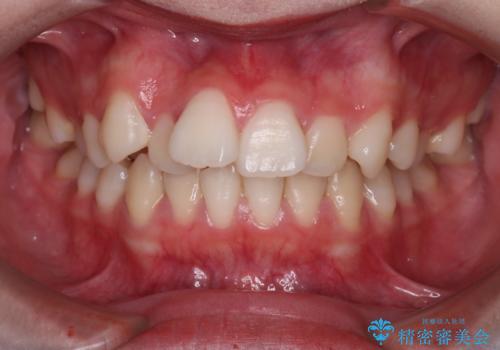

[ 放置し内部で大きく進行した虫歯 ] 神経を守るセラミック治療

担当医 大元洋佑